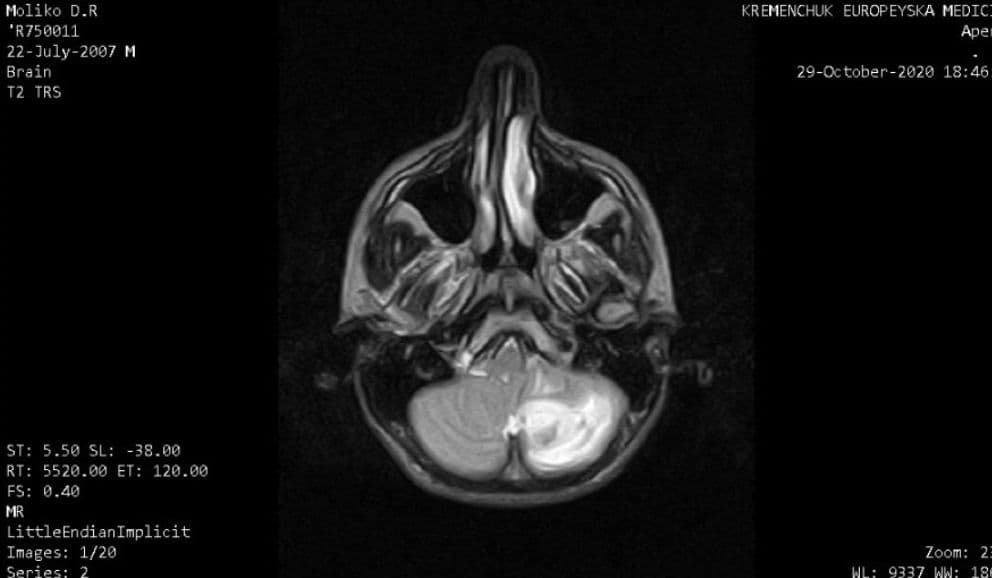

У родини футболіста «Кременя» Владислава Молька захворів брат Денис. У 13-річного хлопця під час МРТ виявили пухлину головного мозку. Лікарі діагностували пухлину у лівій гемісфері мозочку з крововиливом. Юному кременчужанину терміново потрібна операція у київській клініці Охматдет.